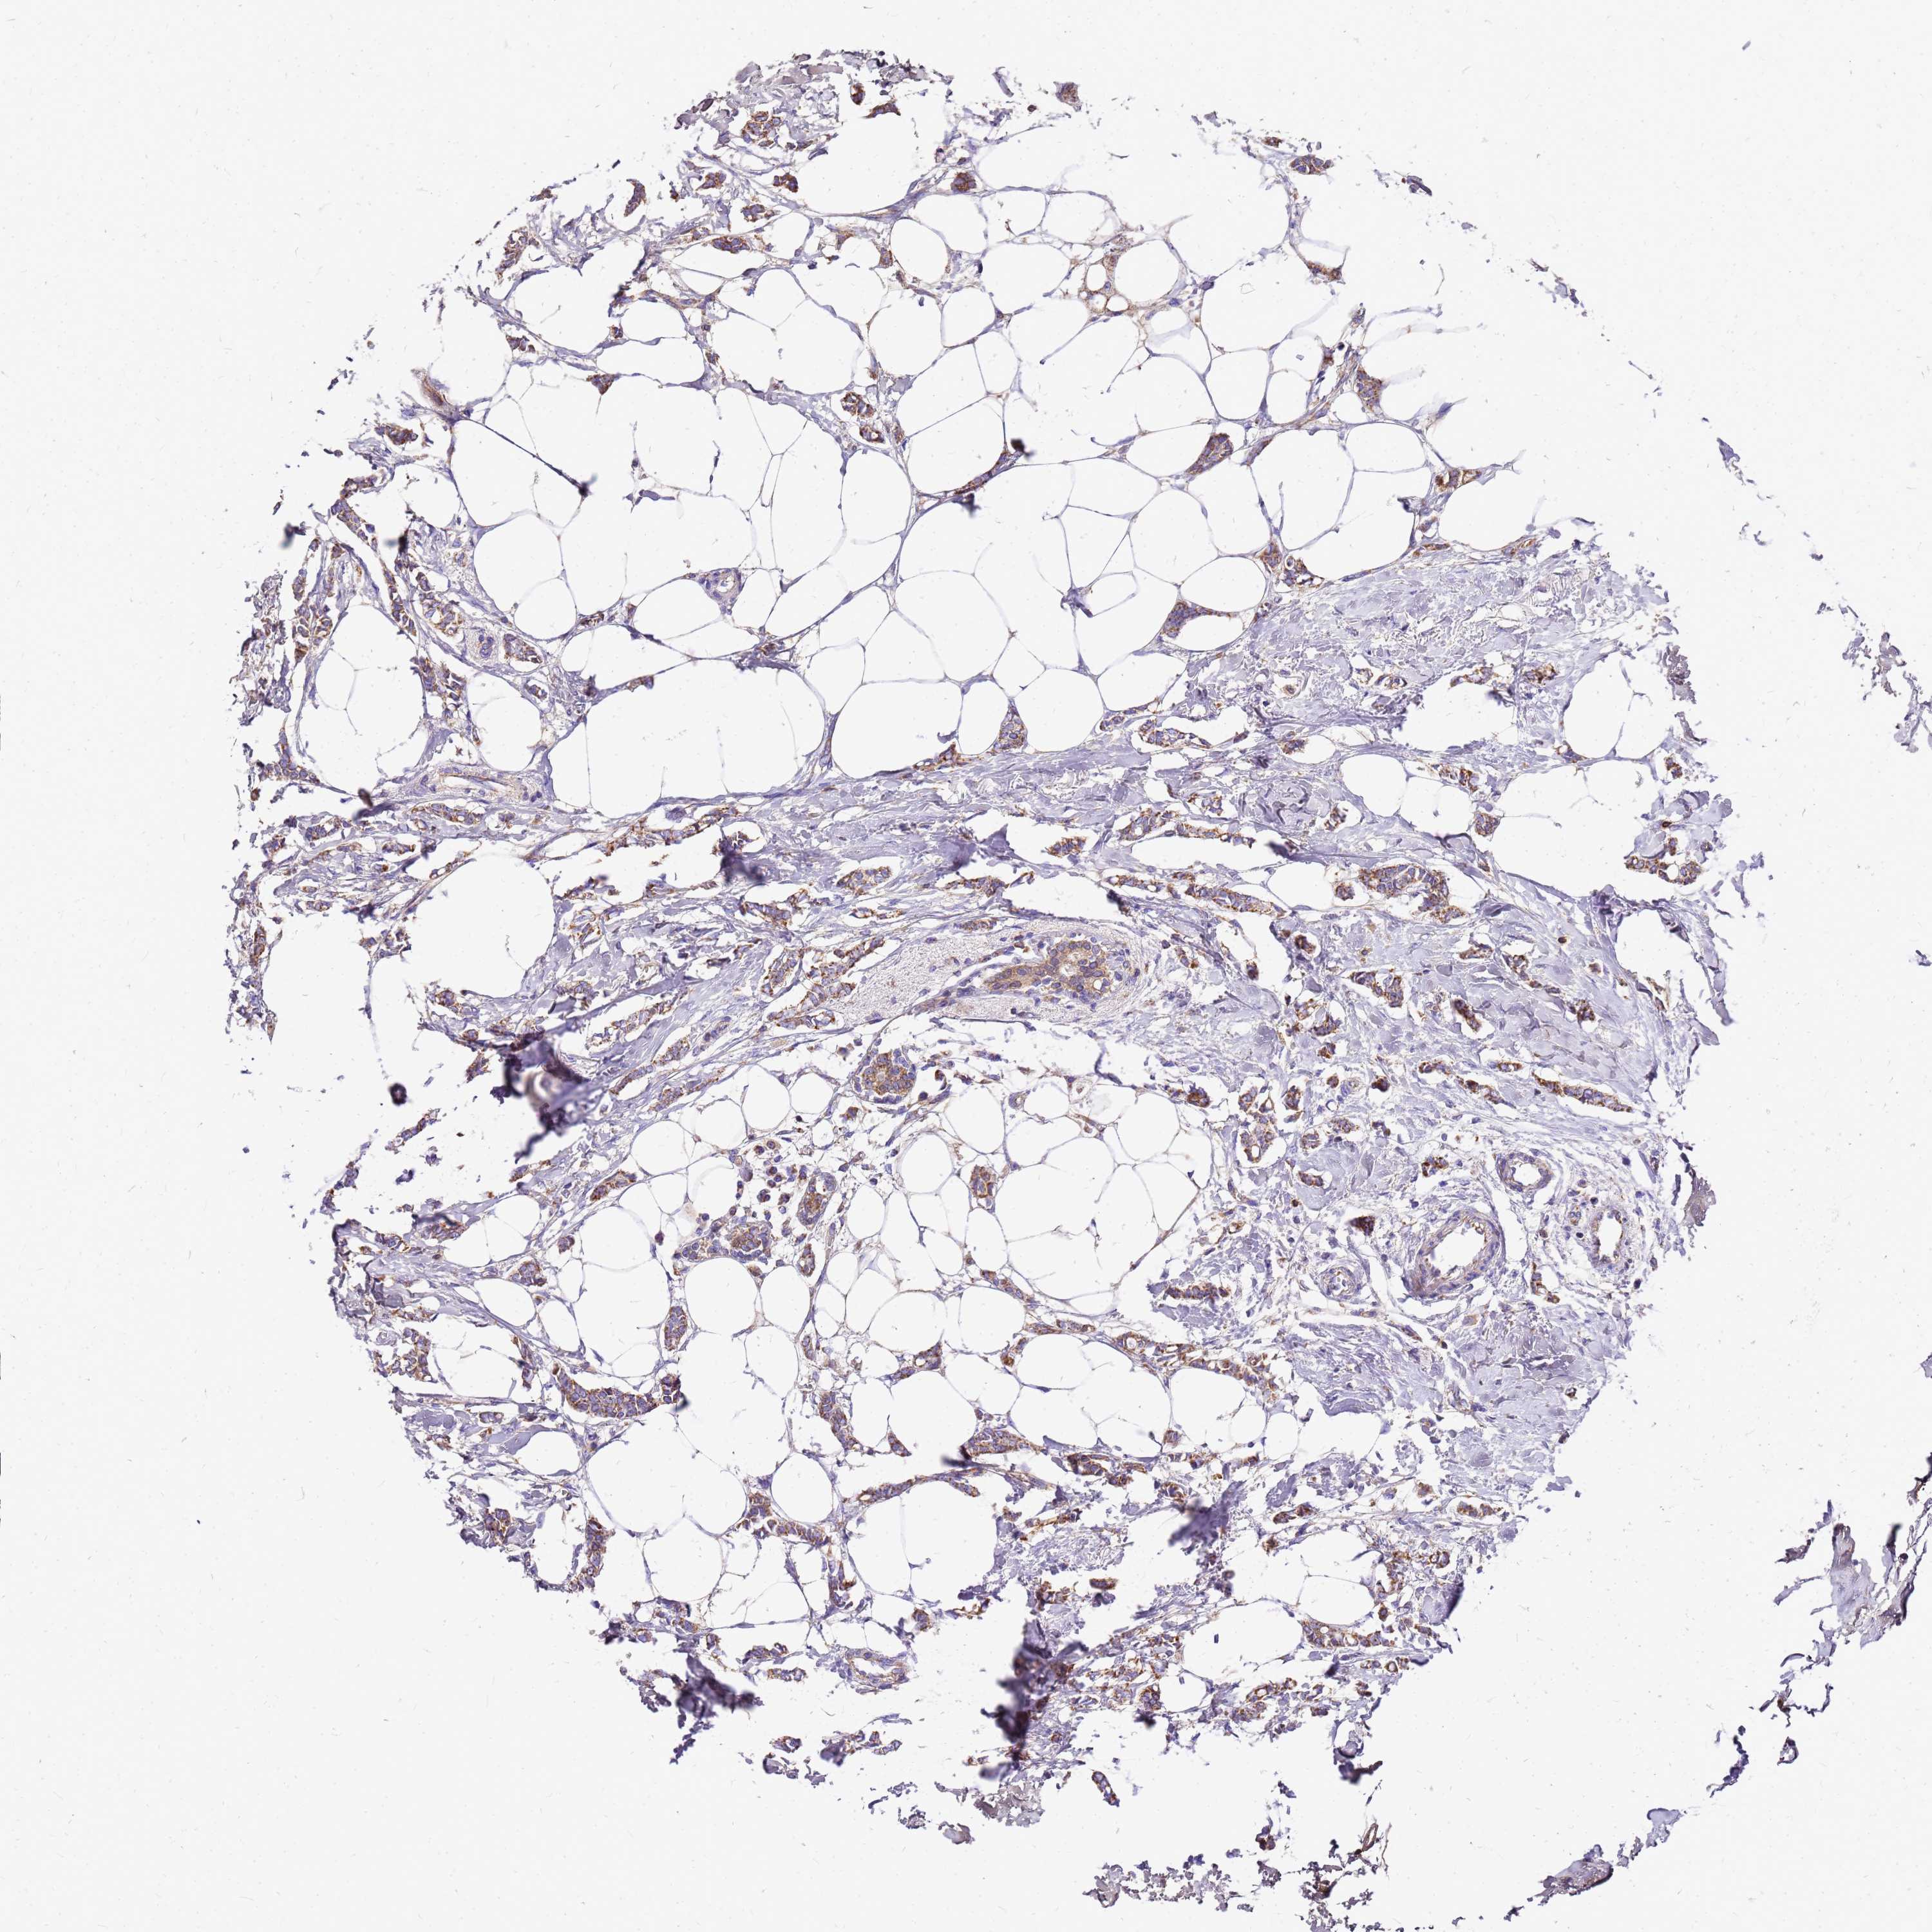

CANCER BREAST CANCER Show tissue menu

BRCA TCGA BRCA VALIDATION PROTEIN EXPRESSION